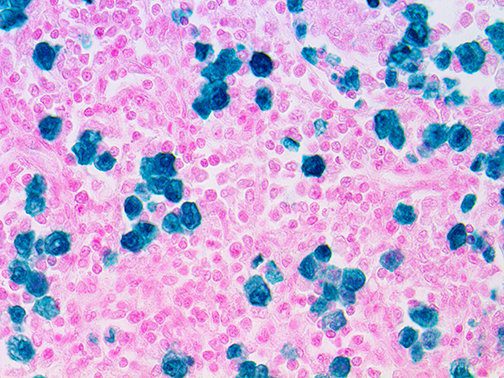

It is the ICU physician who is most likely to witness one of the deadliest manifestations of the abnormal immunological response, the cytokine storm syndrome (CSS). This response is also referred to by some as the cytokine release syndrome (CRS). CSS is characterized by continuous activation and expansion of macrophage and lymphocyte populations, which secrete large amounts of cytokines, causing the cytokine storm. This massive cytokine release is akin to hemophagocytic lymphohistiocytosis (HLH) disease, a syndrome characterized by initial unchecked and persistent activation of cytotoxic T lymphocytes and NK cells.

Clinical and laboratory manifestations of HLH include fever, enlarged liver and/or spleen, neurologic dysfunction, coagulopathy, liver dysfunction, cytopenias (i.e., low levels of erythrocytes, leukocytes, and/or platelets), hypertriglyceridemia, hyperferritinemia, hemophagocytosis, and eventually diminished NK cell activity as the immune system becomes progressively paralyzed. HLH can be familial (primary HLH) or secondary to another disease process (sHLH), such as rheumatic disease, in which it is referred to as macrophage activation syndrome (MAS, characterized by elevated ferritin).